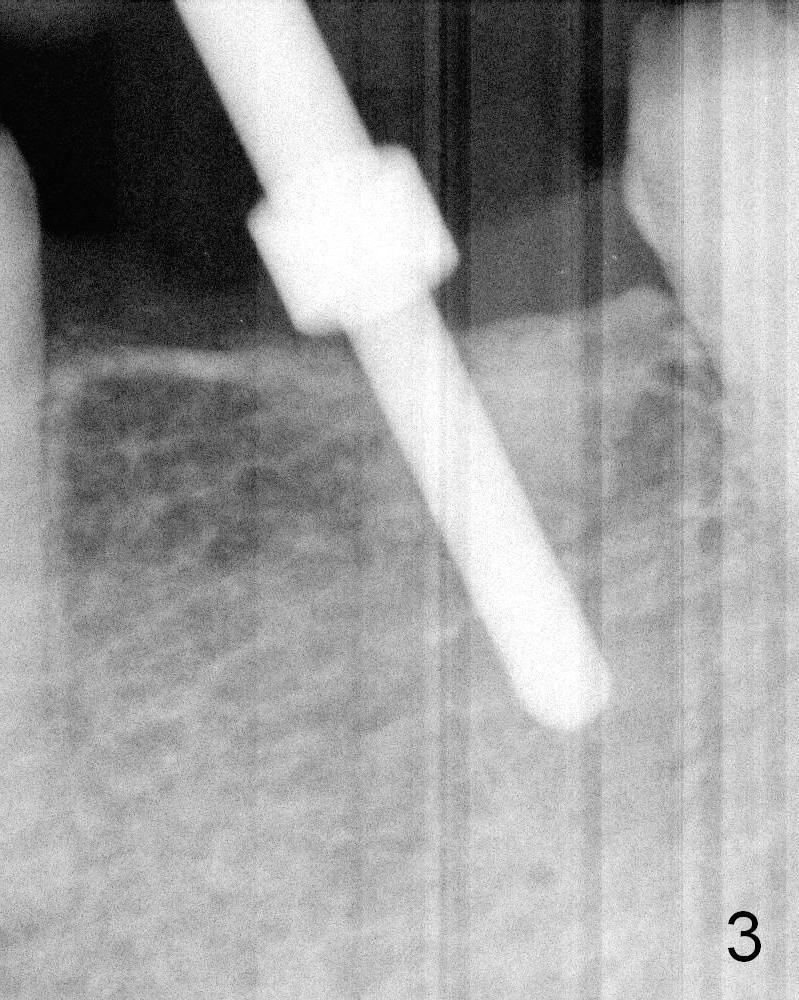

The bone is felt soft during initial osteotomy (Fig.3).   More importantly the parallel pin is not perpendi-cular to the crest.  Ideally after withdrawal of the pin (Fig.3' black area), the trajectory of the osteotomy Should have been corrected so that the drill is perpendi-cular to the crest (red arrow).

Soft Bone of A Smoker